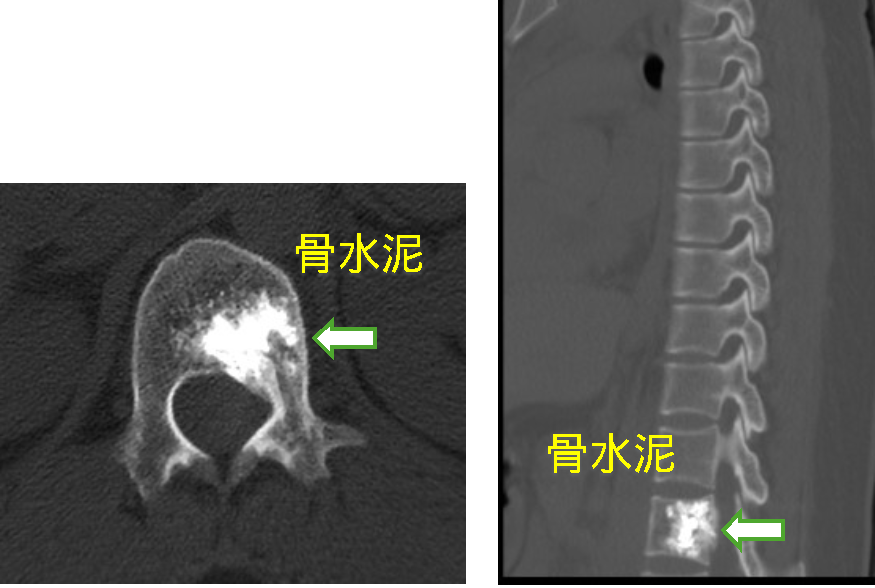

患者一、前列腺癌胸椎脊柱转移行骨水泥注射肿瘤灭活及镇痛术

患者因前列腺脊柱转移导致严重背部疼痛,行骨水泥注射后疼痛完全消失。